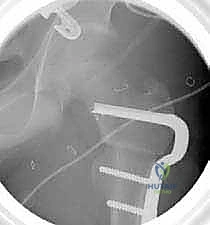

6. التثبيت الداخلي القوي (Internal Fixation)

لضمان التحام العظم في وضعه الجديد، يستخدم الدكتور هطيف نظام تثبيت عالمي يتمثل في صفيحة الشفرة الزاوية (AO 90-degree Blade Plate) أو مسامير وصفيحة مخصصة للأطفال. يتم إدخال الشفرة في عنق الفخذ، وتثبيت الصفيحة على جسم العظم باستخدام براغي معدنية قوية.

7. الإغلاق والتعافي

يتم التأكد من الاستقامة النهائية ومجال الحركة الميكانيكي للمفصل، ثم تُغلق الأنسجة والجلد بخياطة تجميلية دقيقة لتقليل الندبات.